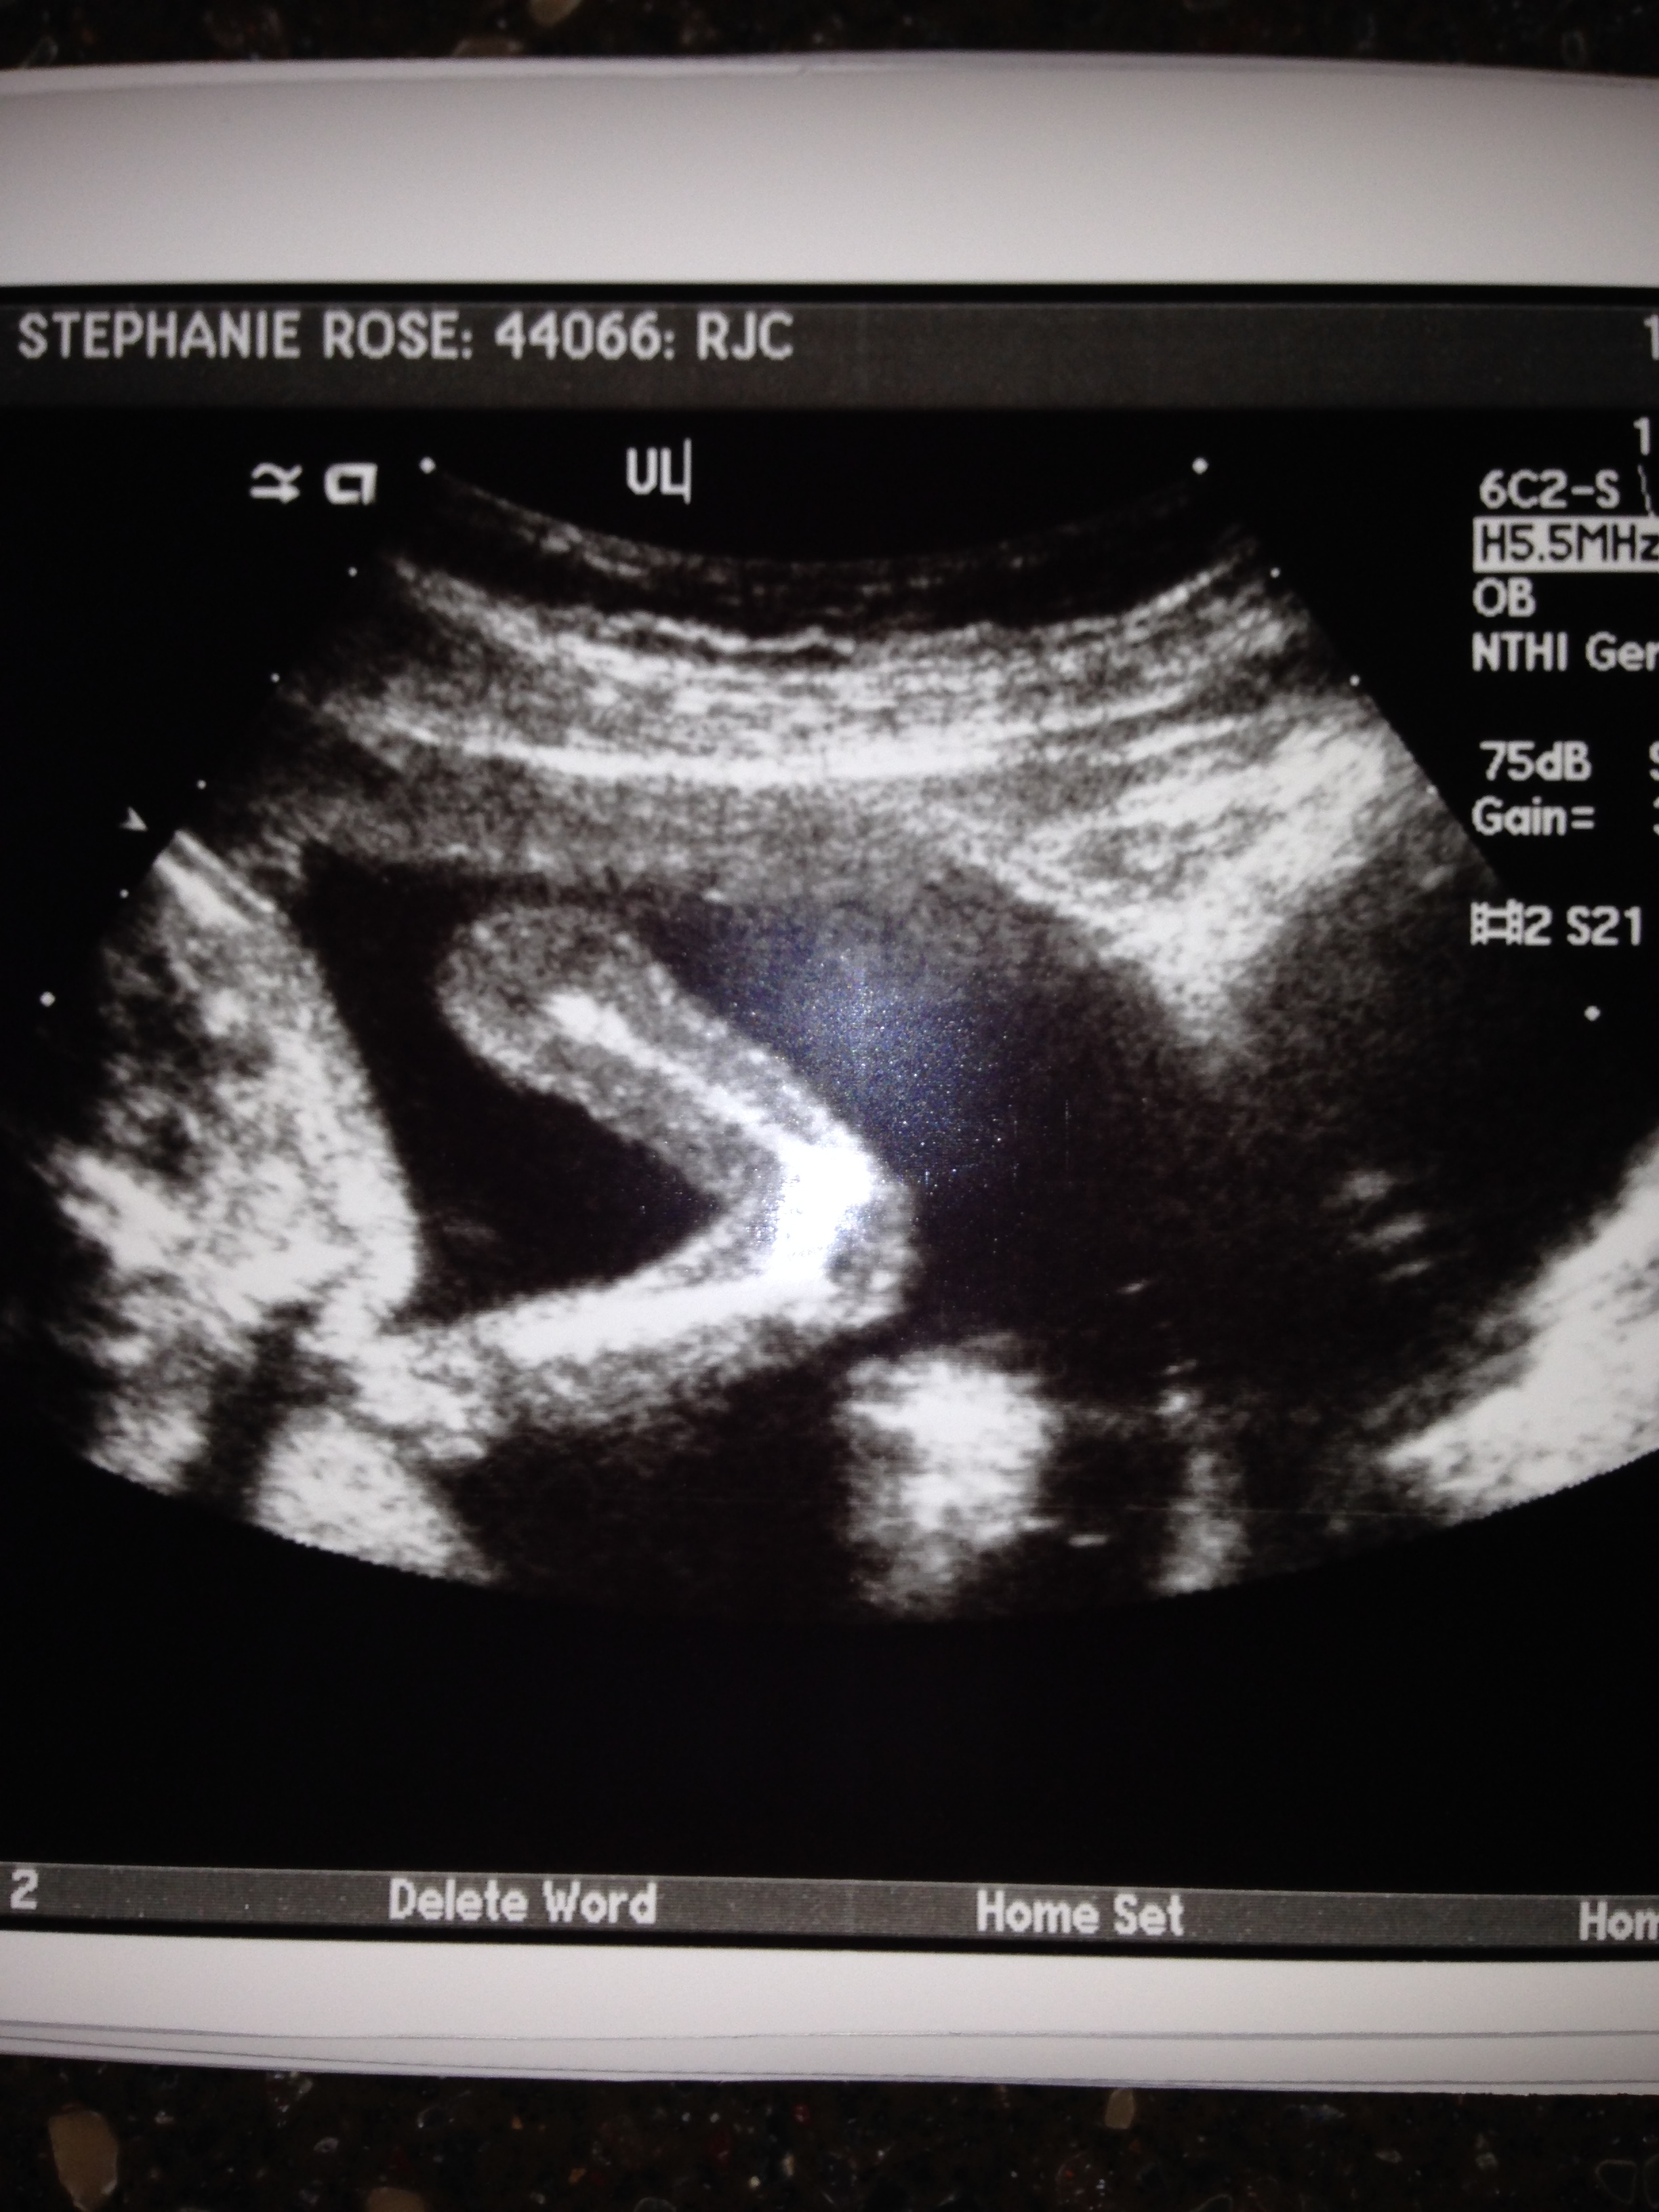

Halloween Sonogram Jeff / October 14, 2013 Just in time for Halloween… Stephanie had another sonogram today and poppy looks like he’s wearing a skull mask. Of course, it’s his actual skull… but still came out looking a little spooky. Share on Facebook (Opens in new window) Facebook Email a link to a friend (Opens in new window) Email Share on X (Opens in new window) X Share on Pinterest (Opens in new window) Pinterest Like Loading...